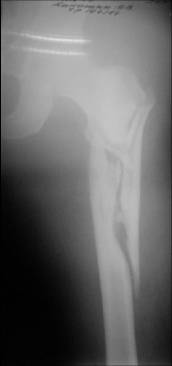

I would use a small wire distractor mentioned in the list some times. Proximal wire is in the iliac crest in AP direction. The leg is adducted. I attached some images. At the AP view under image intensifier you can see adduction but even slight valgus reduction.